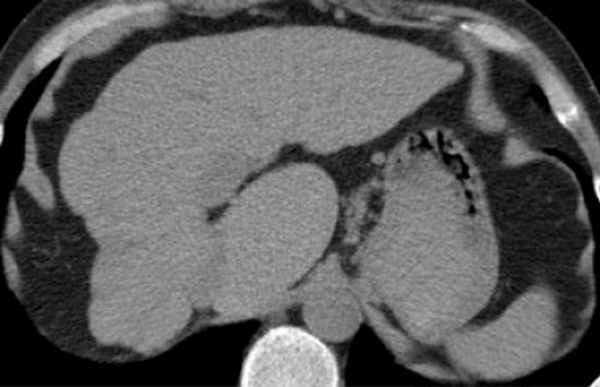

Аксиальное изображение верхних сегментов печени, которые разделены правой и средней печеночной веной и серповидной связкой. Изображение представлено ниже.

Это поперечные изображения на уровне левой воротной вены.

На этом уровне левой воротной вены делит левую долю в верхних отделах (II и IVa) и нижних сегментов (III и IV в).

Левая воротная вена находится на более высоком уровне, чем в правая воротная вена. Изображение представлено ниже.

Аксиальное изображение на уровне правой воротной вены. На данном срезе воротная вена делит правую долю на верхние сегменты ((VII и VIII) и нижние сегменты (V и VI).

Уровень правой воротной вены ниже уровня левой воротной вены. Изображение представлено ниже.

Аксиальное изображение на уровне селезеночной вены, которая находится ниже уровня правой воротной вены, видна только в низко лежащих сегментах. Изображение представлено ниже.

Этот КТ пациента с циррозом печени с атрофией правой доли, с нормальным объемом левой доли и компенсаторной гипертрофией хвостатой доле. Изображение представлено ниже.